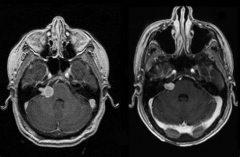

在肿瘤生长的早期,听神经瘤局限于内耳道。患有一期或管内期...